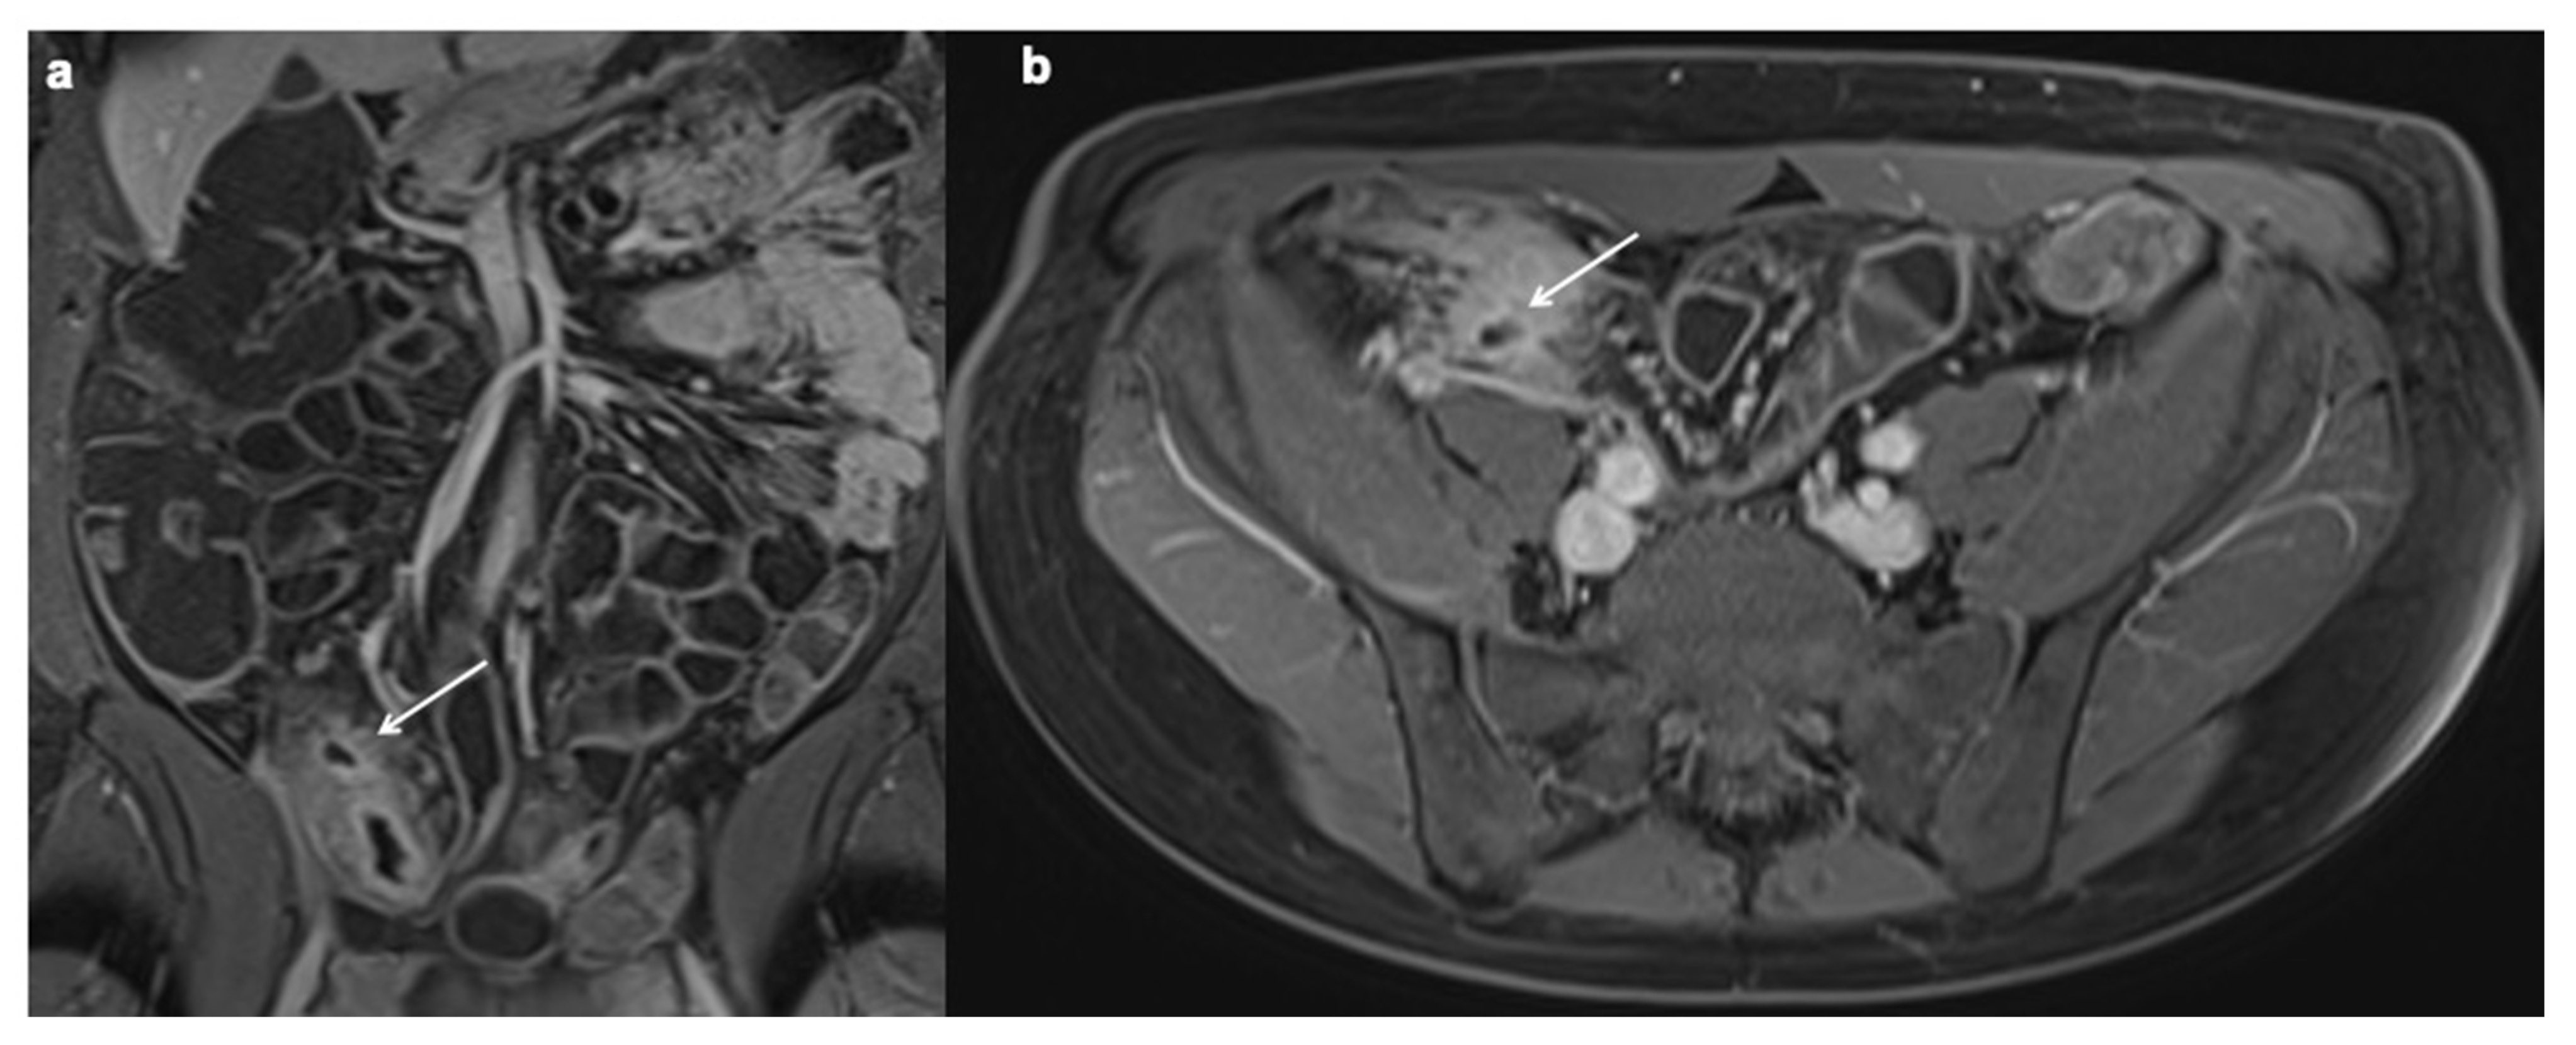

- Gecse, K.B.; Bemelman, W.; Kamm, M.A. A global consensus on the classification, diagnosis and multidisciplinary treatment of perianal fistulising Crohn’s disease. Gut 2014, 63, 1381–1392. [Google Scholar] [CrossRef] [Green Version]

- Bruining, D.H.; Siddiki, H.A.; Fletcher, J.G.; Tremaine, W.J.; Sandborn, W.J.; Loftus, E.V., Jr. Prevalence of penetrating disease and extraintestinal manifestations of Crohn’s disease detected with CT enterography. Inflamm. Bowel Dis. 2008, 14, 1701–1706. [Google Scholar] [CrossRef]

- Booya, F.; Akram, S.; Fletcher, J.G.; Huprich, J.E.; Johnson, C.D.; Fidler, J.L.; Barlow, J.M.; Solem, C.A.; Sandborn, W.J.; Loftus, E.V. CT enterography and fistulizing Crohn’s disease: Clinical benefit and radiographic findings. Gastrointest. Radiol. 2008, 34, 467–475. [Google Scholar] [CrossRef] [PubMed]

- Baker, M.E.; Fletcher, J.G.; Al-Hawary, M.; Bruining, D. Interdisciplinary Updates in Crohn’s Disease Reporting Nomenclature, and Cross-Sectional Disease Monitoring. Radiol. Clin. N. Am. 2018, 56, 691–707. [Google Scholar] [CrossRef] [PubMed]

- Parks, A.G.; Gordon, P.H.; Hardcastle, J.D. A classification of fistula-in-ano. Br. J. Surg. 1976, 63, 1–12. [Google Scholar] [CrossRef] [PubMed]